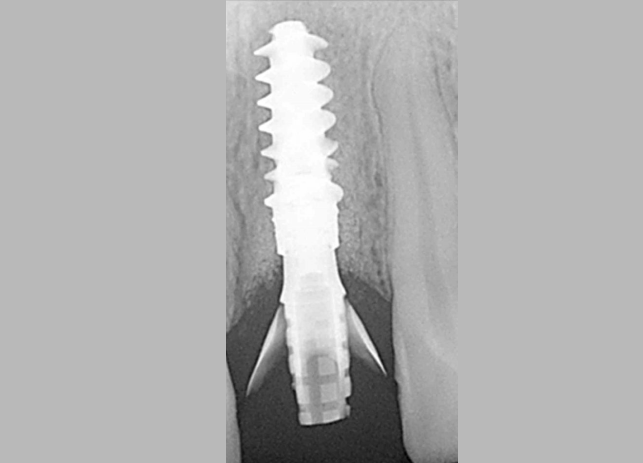

Этот пациент обратился ко мне с жалобами на сильную боль, покраснение и отек вокруг только что установленной коронки на имплантате. В анамнезе было следующее: был снят аналоговый оттиск с уровня имплантата и отправлен в лабораторию для изготовления коронки. У лаборанта не было указаний относительно расположения шейки имплантата по отношению к мягким тканям и кости.

Была выбрана самая короткая высота десневой манжеты (GH), так как она является наиболее безопасной с эстетической точки зрения, поскольку металлическая кромка не будет видна над десной. При доставке коронки на имплантат стоматолог столкнулся с трудностями при «посадке» коронки на абатмент.

Коронка была установлена со значительным сопротивлением для достижения необходимого значения торка. Ущемление твердых и мягких тканей из-за очень острого профиля выступа вызывает давление на кость, что приводит к некрозу и, в конечном итоге, к потере маргинальной кости в этой области. Чтобы избежать подобных осложнений, необходимо выбирать правильный абатмент.

На основе ОПТГ, сделанного после установки или имплантата (рис. 2), стоматолог может выбрать подходящую высоту десневой манжеты для абатмента и направить техника, предоставив рентгеновский снимок и/или спецификацию формирователя десны. Большинство систем имплантатов имеют синхронизированные формы и контуры хирургических абатментов и компонентов протеза.